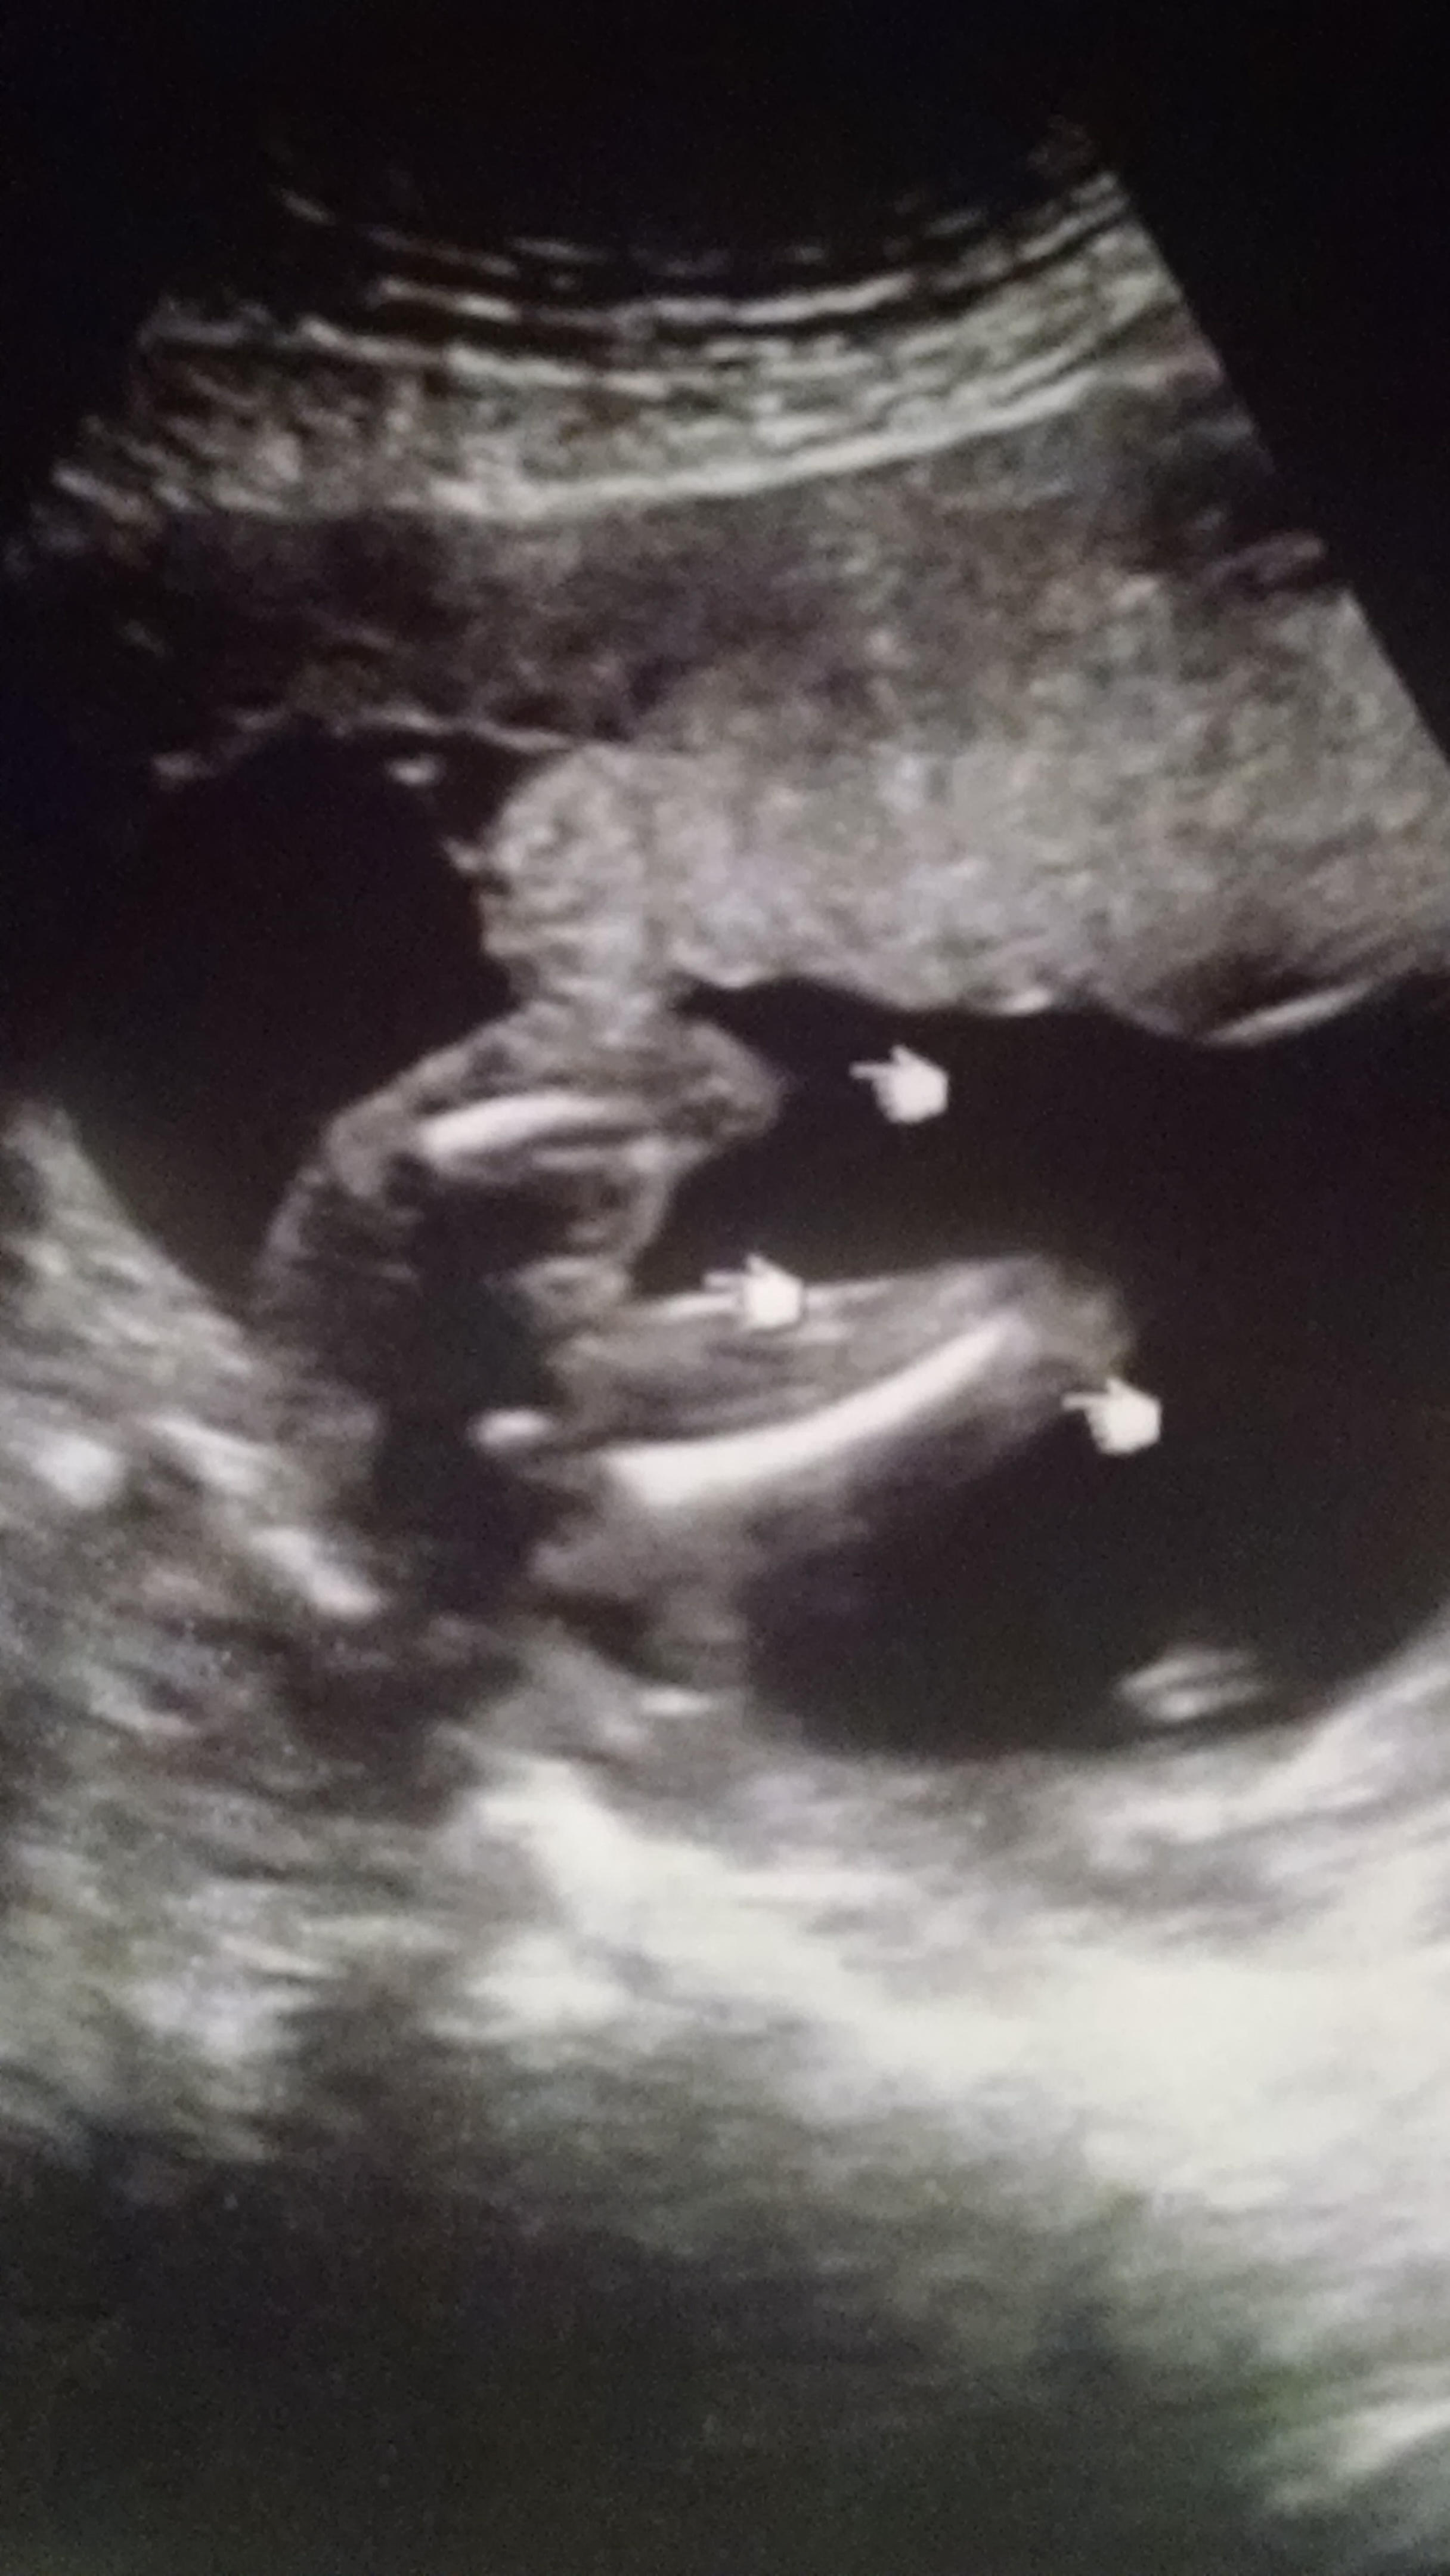

My husband and I went to our ultrasound and I was 18 weeks and 6 days. The Dr said it was a girl right away because there was nothing between the legs. He looked for maybe a few seconds. I don't see any white lines and am wondering if you thing boy or girl?